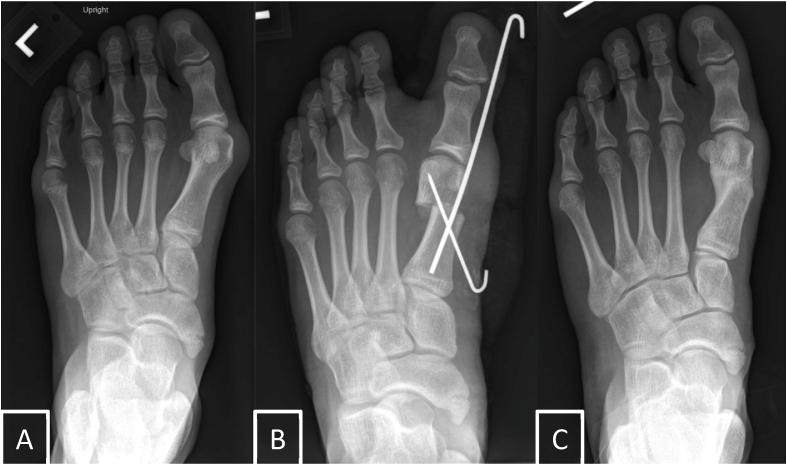

In adults, minimally invasive surgery for surgical treatment of hallux valgus has become increasingly popular, with a growing body of literature showing safety and effectiveness comparable to open surgery. Minimally invasive techniques for the treatment of juvenile hallux valgus include Bosch, Reverdin-Isham, Chevron, Endolog, distal soft tissue release, and hemiepiphysiodesis procedures. Data comparing minimally invasive and open surgery for the treatment of juvenile hallux valgus in children and adolescents are limited. In this review, we provide an overview of juvenile hallux valgus, discuss the minimally invasive techniques available for surgical treatment, and review the data on safety and effectiveness associated with each technique. There is a need for larger-scale studies comparing minimally invasive and open surgery for the treatment of juvenile hallux valgus, as well as the development of a standardized set of clinical and radiographic outcomes to guide evidence-based surgical management of juvenile hallux valgus.

(1)Compared with data on managing hallux valgus in adults, information on the safety and effectiveness of minimally invasive surgery for treating juvenile hallux valgus is limited.(2)Minimally invasive techniques for treating juvenile hallux valgus include Bosch, Reverdin-Isham, Chevron, Endolog, distal soft tissue release, and hemiepiphysiodesis procedures.(3)In total, 10 studies have assessed outcomes, demonstrating varying degrees of radiographic and clinical improvement along with complication rates.(4)Future large-scale comparative studies and standardized outcomes are essential for informing evidence-based surgical management of juvenile hallux valgus.